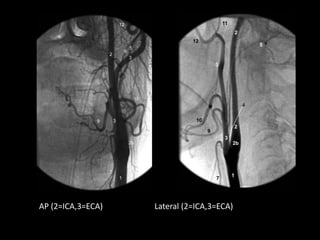

c) Course :

-It arises at the level of the superior border of the

thyroid cartilage and terminates beneath the neck of

the mandible by dividing into superficial temporal

and internal maxillary arteries

-At its origin , it is situated Anterior to the ICA but as it

ascends , it lies more Posteriorly and finally Lateral to

ICA (APL)

-Thus , on frontal angiography its origin is medial to the

ICA origin and the vessels reverse their relative

positions as they run superiorly but on the lateral

view the ICA is always posterior

AP (2=ICA,3=ECA) Lateral (2=ICA,3=ECA)